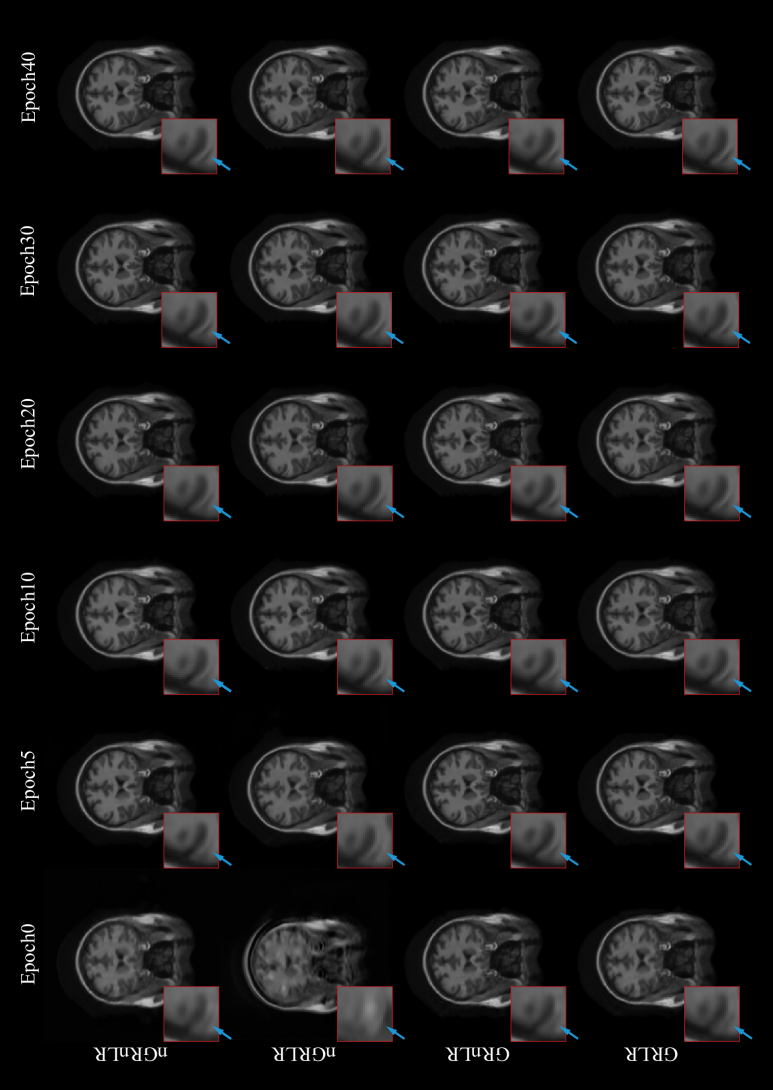

In this experiment, the effect of residual learning in the network was discussed. Our proposed model was tested on MICCAI 2013 grand challenge dataset, using Gaussian 1D 30% downsampling.

The experiment was divided into four groups: (1) GRLR (model with GR and LR), (2) GRnLR (model with GR without LR), (3) nGRLR (model with LR without GR), (4) nGRnLR (model without LR and GR). Early stopping strategy was turned off in this experiment to prolong the training process for a better and more distinguishable comparison for the training step.

Fig. 12 shows NMSE, SSIM, PSNR and generator loss (G Loss) of the four groups changing with the training process, and Fig. 13 shows testing examples with respect to different epoch weights.

Models with GR (GRLR, GRnLR) have faster convergence and better final results compared with those without GR (nGRLR, nGRnLR). If the model applies GR, then using LR has little further impact effect on the results. For non-GR models, nGRLR converges significantly slower than nGRnLR but final results are superior. Therefore, we chose GRLR as the generator for subsequent study.